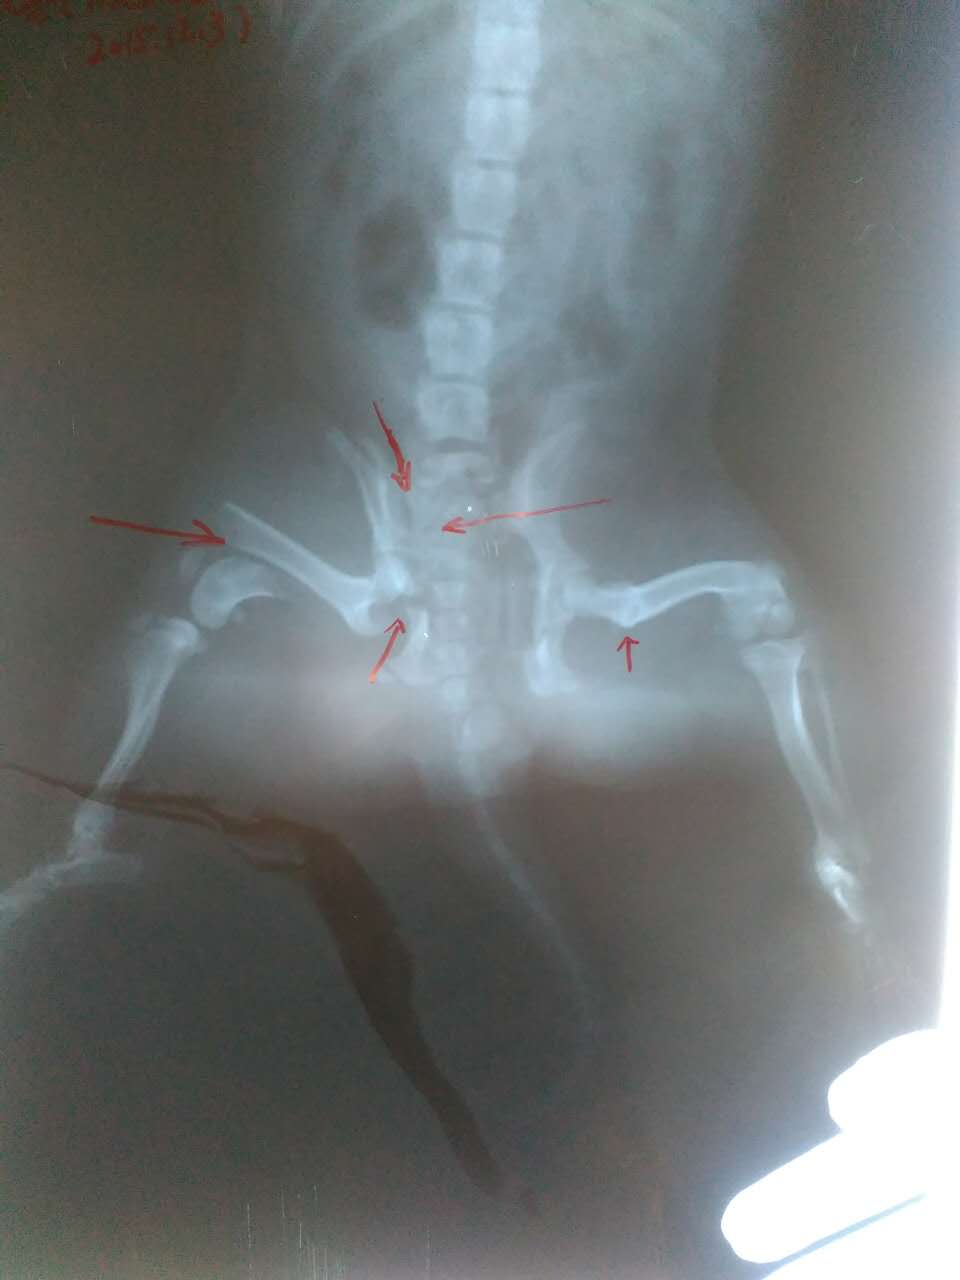

可愛(ài)斗牛犬胯骨股骨嚴(yán)重骨折,術(shù)后痊愈!